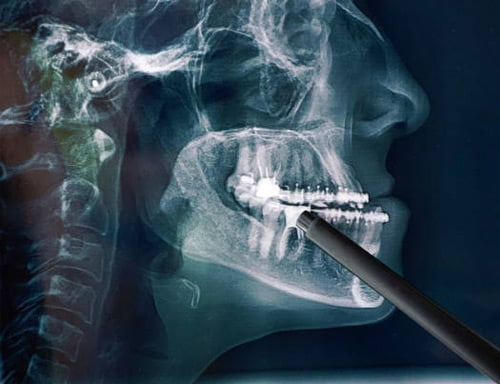

Cirurgia Crânio-Maxilo-Facial

A Cirurgia Crânio-Maxilo-Facial, também conhecida por Cirurgia Craniofacial, é uma área de atuação médica, das Especialidades de Cirurgia Plástica, Otorrinolaringologia e Cirurgia de Cabeça e Pescoço.

Possui cinco segmentos principais:

a – anomalias congênitas (ex: microssomais craniofaciais, Sequência de Pierre Robin, fendas lábio palatinas)

b – fraturas de face

c – tumores do esqueleto craniofacial

d – alterações de desenvolvimento do esqueleto craniofacial (alterações dento-esqueléticas como prognatismo e retrognatismo)

e – ronco/apnéia do sono (cirurgia ortognática, expansão de maxilar, faringoplastia por cirurgia robótica).

Os conhecimentos adquiridos nas últimas décadas têm possibilitado a reabilitação funcional, estética e social de pacientes com diversas patologias no segmento craniofacial, através da íntima relação com outros profissionais de saúde, pois uma abordagem multidisciplinar é o melhor caminho para um atendimento eficaz e de qualidade.